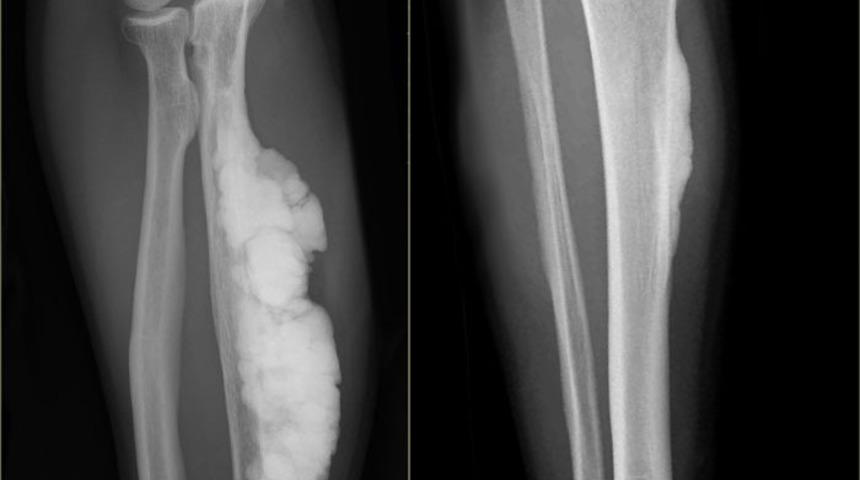

RÖNTGEN TESTLERİ İLE ORTAYA ÇIKIYOR

Yıldırım, “Bu hastalığın gözle görülür bir belirtisi yoktur. Hastalarda genellikle 40 yaşından sonra yapılan sağlık taramaları ve röntgen testleri ile birlikte ortaya çıkabilir ve en sık rastlanan belirtisi kemik ağrısıdır. Yapı olarak bozuk iskelet dokusu gelişir ve bu da kırık riskinde artışla birlikte kemikte şekil bozukluğuna neden olur.